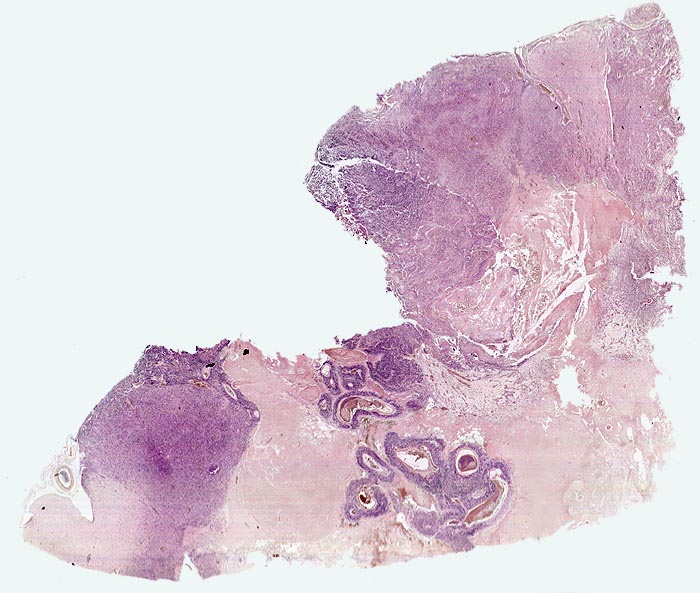

Morphologische Merkmale:

• Zellreicher Tumor mit sehr unscharfer Begrenzung zum normalen Hirnparenchym (rechts unten).

• Typische streifenförmige Nekrosen mit randständiger Palisadierung der Tumorzellen.

• Im Zentrum der Nekrose thrombosierte Gefässe umgeben von einem Saum vitaler Tumorzellen.

• Pathologische glomerulumartige zellreiche Gefässknäuel.

• Ausgeprägte Zellpolymorphie und Atypie.

• Mitosen.

Virtuelles Präparat